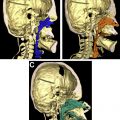

Before the introduction of virtual surgical planning (VSP) and three-dimensional (3D) printing technology to craniofacial surgery, several studies documented the associated detrimental effects of MDO on (1) injury to developing tooth buds, (2) deformational growth effects on the mandible, (3) facial soft tissue scarring, (4) inferior alveolar nerve damage, and (5) mandibular hypomotility caused by TMJ ankyloses. However, the more recent experience of MDO in patients with TCS has been favorable with the introduction of computer-assisted design and computer-assisted manufacturing, which enables surgeons to design osteotomy guides and simulate hardware placement virtually ( Fig. 3 ). In our experience, VSP osteotomy guides substantially decrease the risk of iatrogenic injury to the inferior alveolar nerve or tooth buds, and preoperative simulation also allows finer control of the distraction vector. VSP has also been shown to help craniofacial surgeons perform preplanned mandibular and curvilinear distraction with a high degree of accuracy across a variety of surgical approaches, and has been associated with improved outcomes among patients receiving other forms of mandibular reconstruction.

Given the benefits associated with VSP and the inherently challenging morphology seen in patients with TCS, the senior author routinely uses VSP before any TCS-related MDO in order to improve clinical outcomes. The senior author acquires a preoperative maxillofacial CT scan in all surgical patients with TCS and performs virtual simulation of the procedure with an industry partner that provide VSP services.